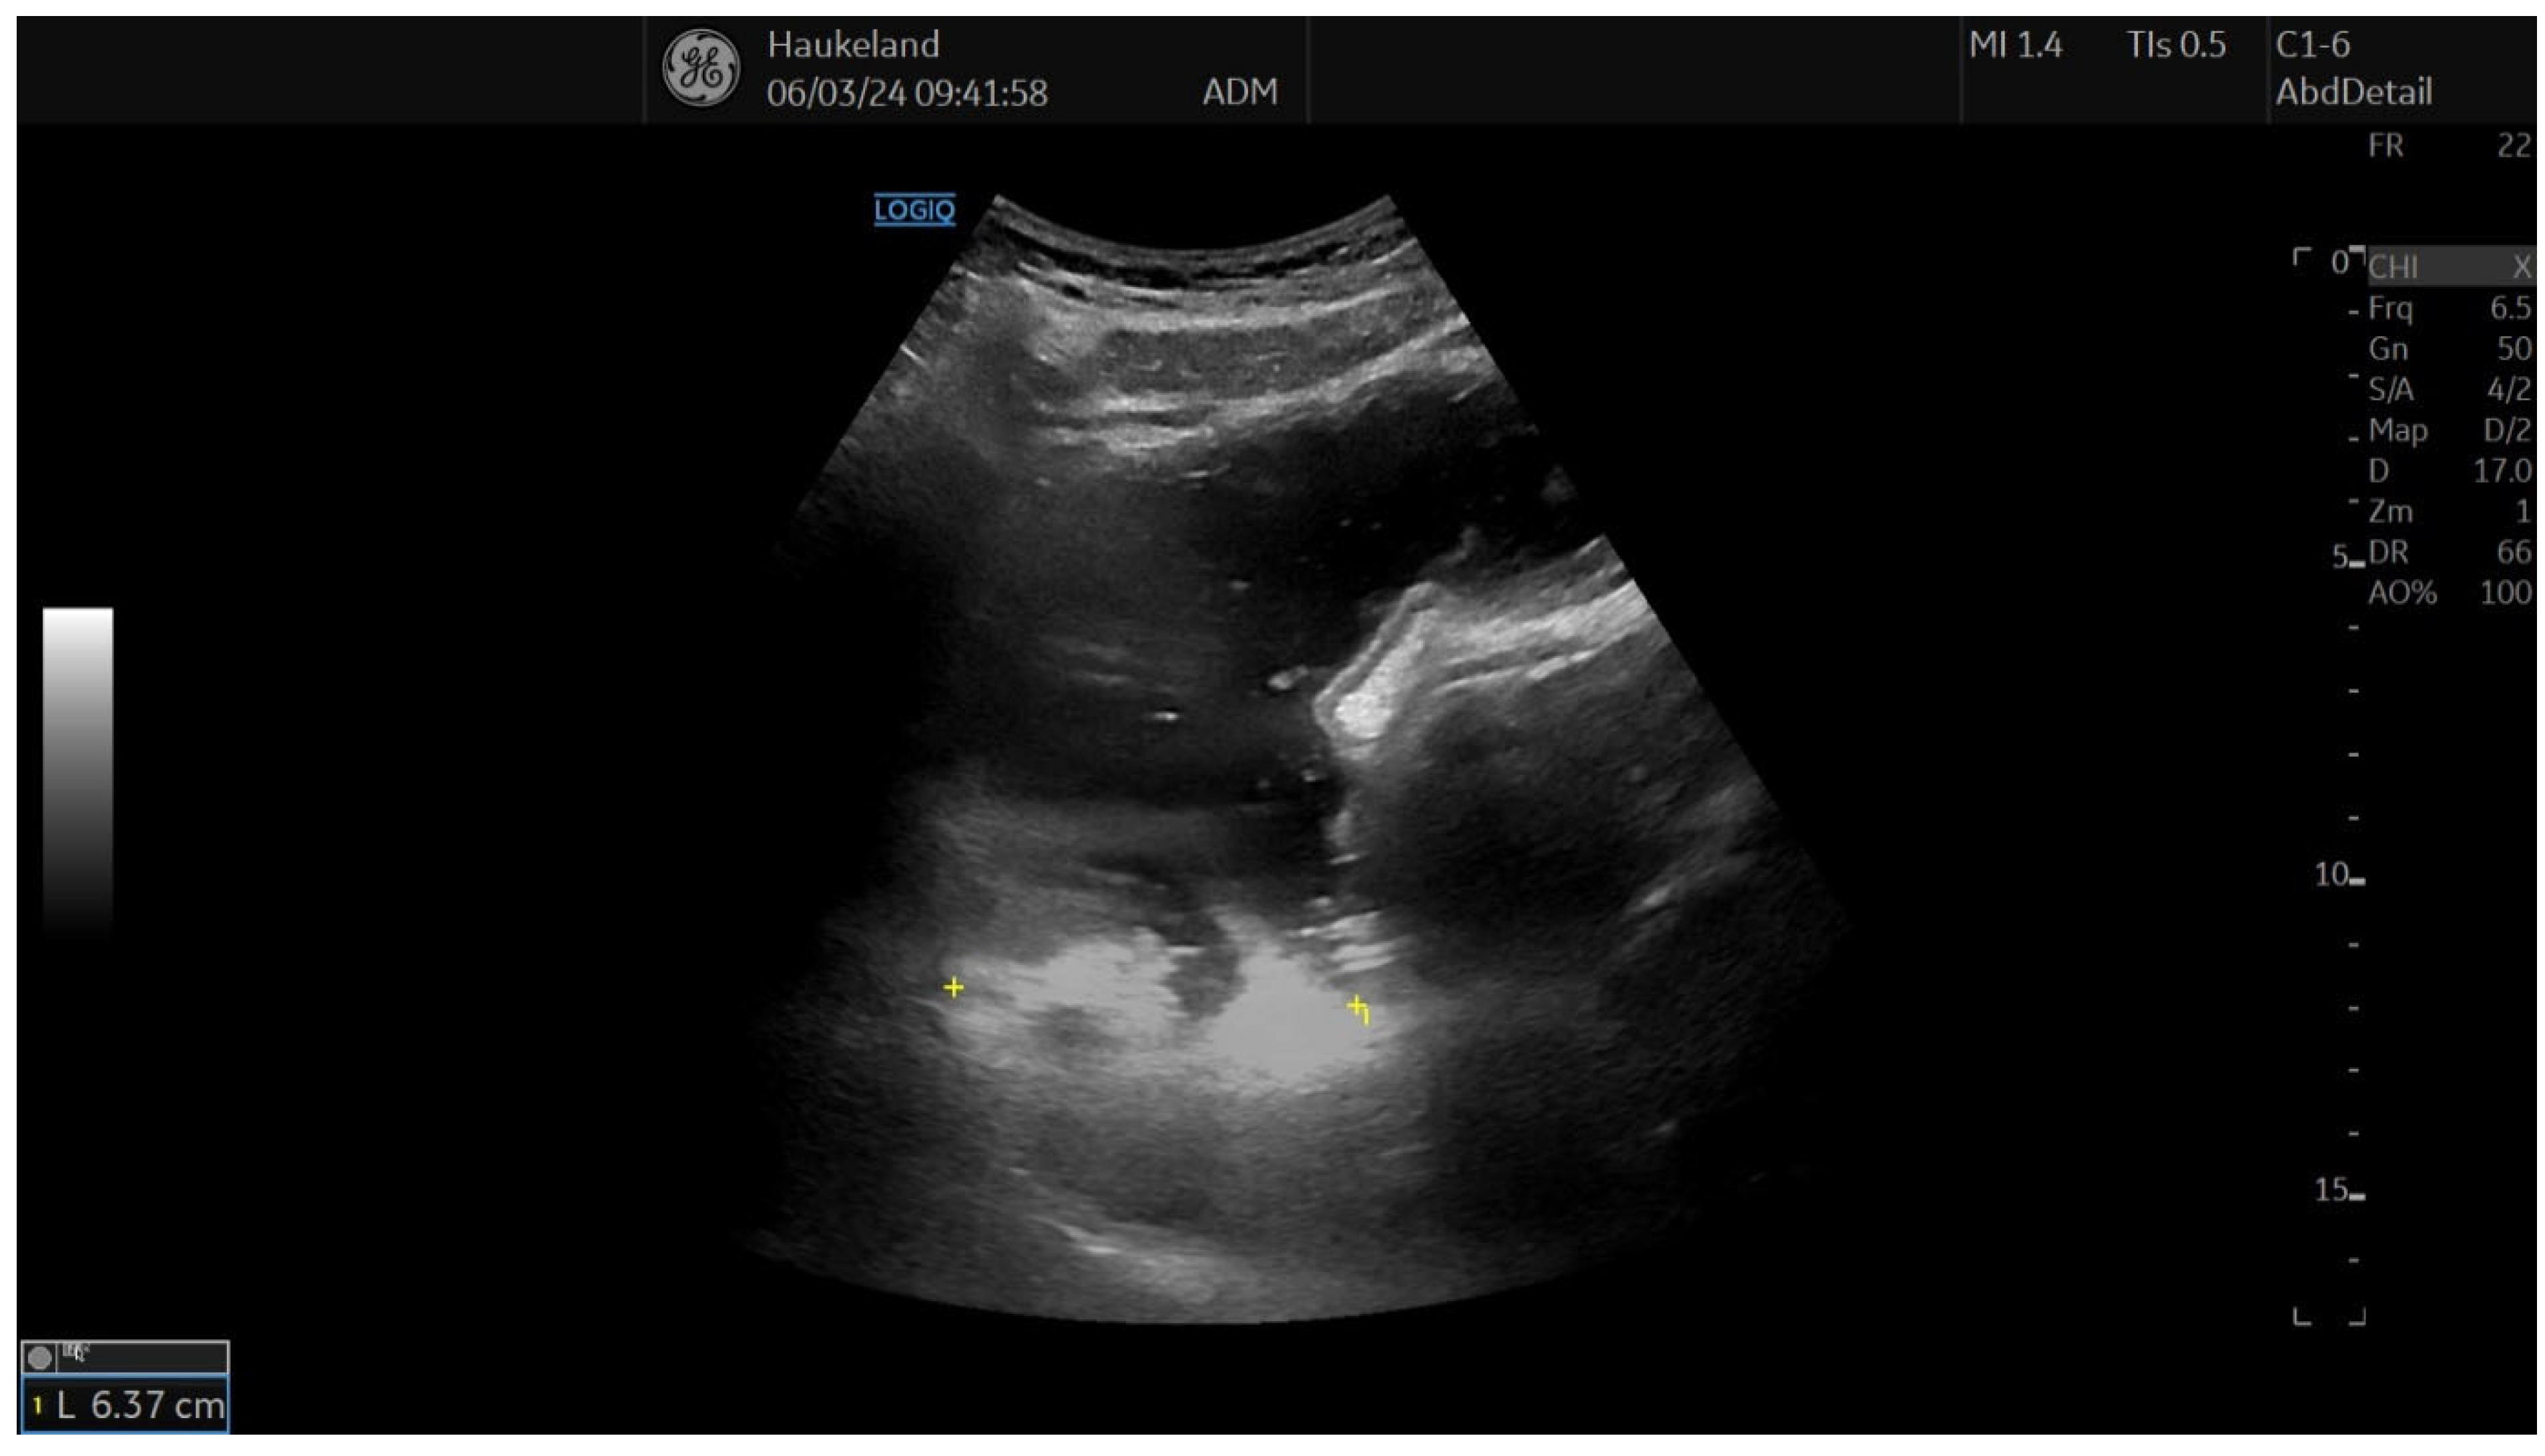

The most common method applied to assess proximal gastric accommodation was by assessing changes in proximal gastric area (PGA) and maximal proximal gastric diameter (MPGD). Changes in PGA and MPGD after meal ingestion were used as indirect measurements of proximal gastric volume changes, thus reflecting gastric accommodation. To obtain PGA, the transducer was placed in the epigastrium longitudinally under the left subcostal margin and tilted cranially in the long axial direction [11,12,18,22]. This allowed for a visualization of a sagittal section of the proximal stomach, and internal landmarks were the left kidney in the longitudinal projection, the left lobe of the liver, and the tail of the pancreas [11,12,18,22]. On the sagittal section, PGA was calculated by tracing along the luminal echogenic surface, which corresponded to the interface between the gastric liquid and the mucosa of the gastric wall (Figure 3) [11,12]. This was performed from the top margin of the fundus to 7 cm inferiorly along the axis of the proximal stomach (Figure 3) [11,12,18,22]. MPGD was obtained from an oblique frontal section (transverse section), which was achieved by rotating the probe 90° clockwise and tilting it cranially in the short axial direction [11,12,18,22]. The landmarks to look for in the transverse section were the left hemidiaphragm, the top margin of the fundus, and the liver parenchyma [11,12,18,22]. The diameter was measured within the 7 cm long axis of the proximal stomach (Figure 4) [18,22].

Figure 4. This image shows the measurement of the maximal proximal gastric diameter (MPGD) using 2D-US, which is used to assess gastric accommodation. MPGD was obtained by rotating the transducer 90° clockwise after holding it in the position to obtain PGA and tilting it cranially in the short axial direction. Internal landmarks to look for were the left hemidiaphragm, top margin of the fundus, and liver parenchyma. The diameter was measured within the 7 cm long axis of the proximal stomach. This image was taken after meat soup ingestion as part of the UMAT at Haukeland University Hospital, Bergen, Norway.